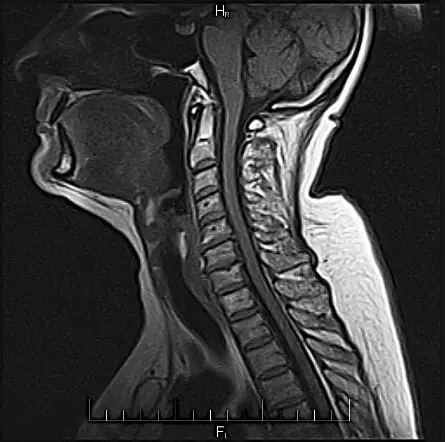

Дивлячись на МРТ шиї, лікар уточнює структуру верхніх дихальних шляхів, їх прохідність, тканини що поруч.

Грижі такого розміру можуть не давати ніякої симптоматики. Тобто не супроводжуватися болем.

На знімку МРТ, який представлений нижче, видно не тільки нижній шийний відділ хребта, але і грудний. Вдале поєднання, так як шийно-грудне з’єднання часто є причиною больових відчуттів: